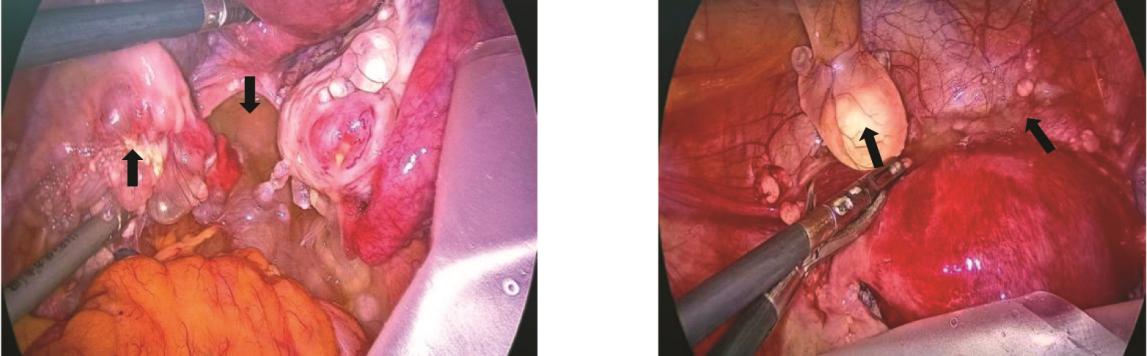

Noiret B, Renaud F, Piessen G, et al. Multicystic peritoneal mesothelioma: a systematic review of the literature[J]. Pleura Peritoneum, 2019, 4(3):20190024. doi: 10.1515/pp-2019-0024.

Zhang CH, Yu JW, Luo M. Multicystic peritoneal mesothelioma: A short review[J]. Curr Probl Cancer, 2017, 41(5):340-348. doi: 10.1016/j.currproblcancer.2017.03.002.

Incesu MM, Ucar M, Kozan R, et al. Benign Multicystic Peritoneal Mesothelioma: Two Rare Cases and Review of the Literature[J]. Curr Med Imaging, 2023 Nov 7. doi: 10.2174/0115734056246439231023111720.Epubaheadofprint.

Oshikiri H, Ozawa Y, Suzuki O, et al. Benign multicystic peritoneal mesothelioma occurring in bilateral inguinal canals metachronously: a case report[J]. Surg Case Rep, 2022, 8(1):44. doi: 10.1186/s40792-022-01399-5.

Ceylan AT, Maila A, Aziz Hakki C, et al. Benign multicystic peritoneal mesothelioma mimicking mucinous ovarian neoplasm with pseudomyxoma peritonei[J]. BMJ Case Reports, 2023, 16(3):e254116. doi: 10.1136/bcr-2022-254116.

Wu CC, Bassi A, Onitilo A, et al. Intra-Operative Diagnosis of Benign Multicystic Peritoneal Mesothelioma: A Case Report of Rare Entity and Lessons Learned[J]. Cureus, 2024, 16(5):e60664. doi: 10.7759/cureus.60664.

Wassef J, Kim J, Farag T, et al. A case of benign multicystic peritoneal mesothelioma[J]. J Surg Case Rep, 2024, 2024(10):rjae629. doi: 10.1093/jscr/rjae629.